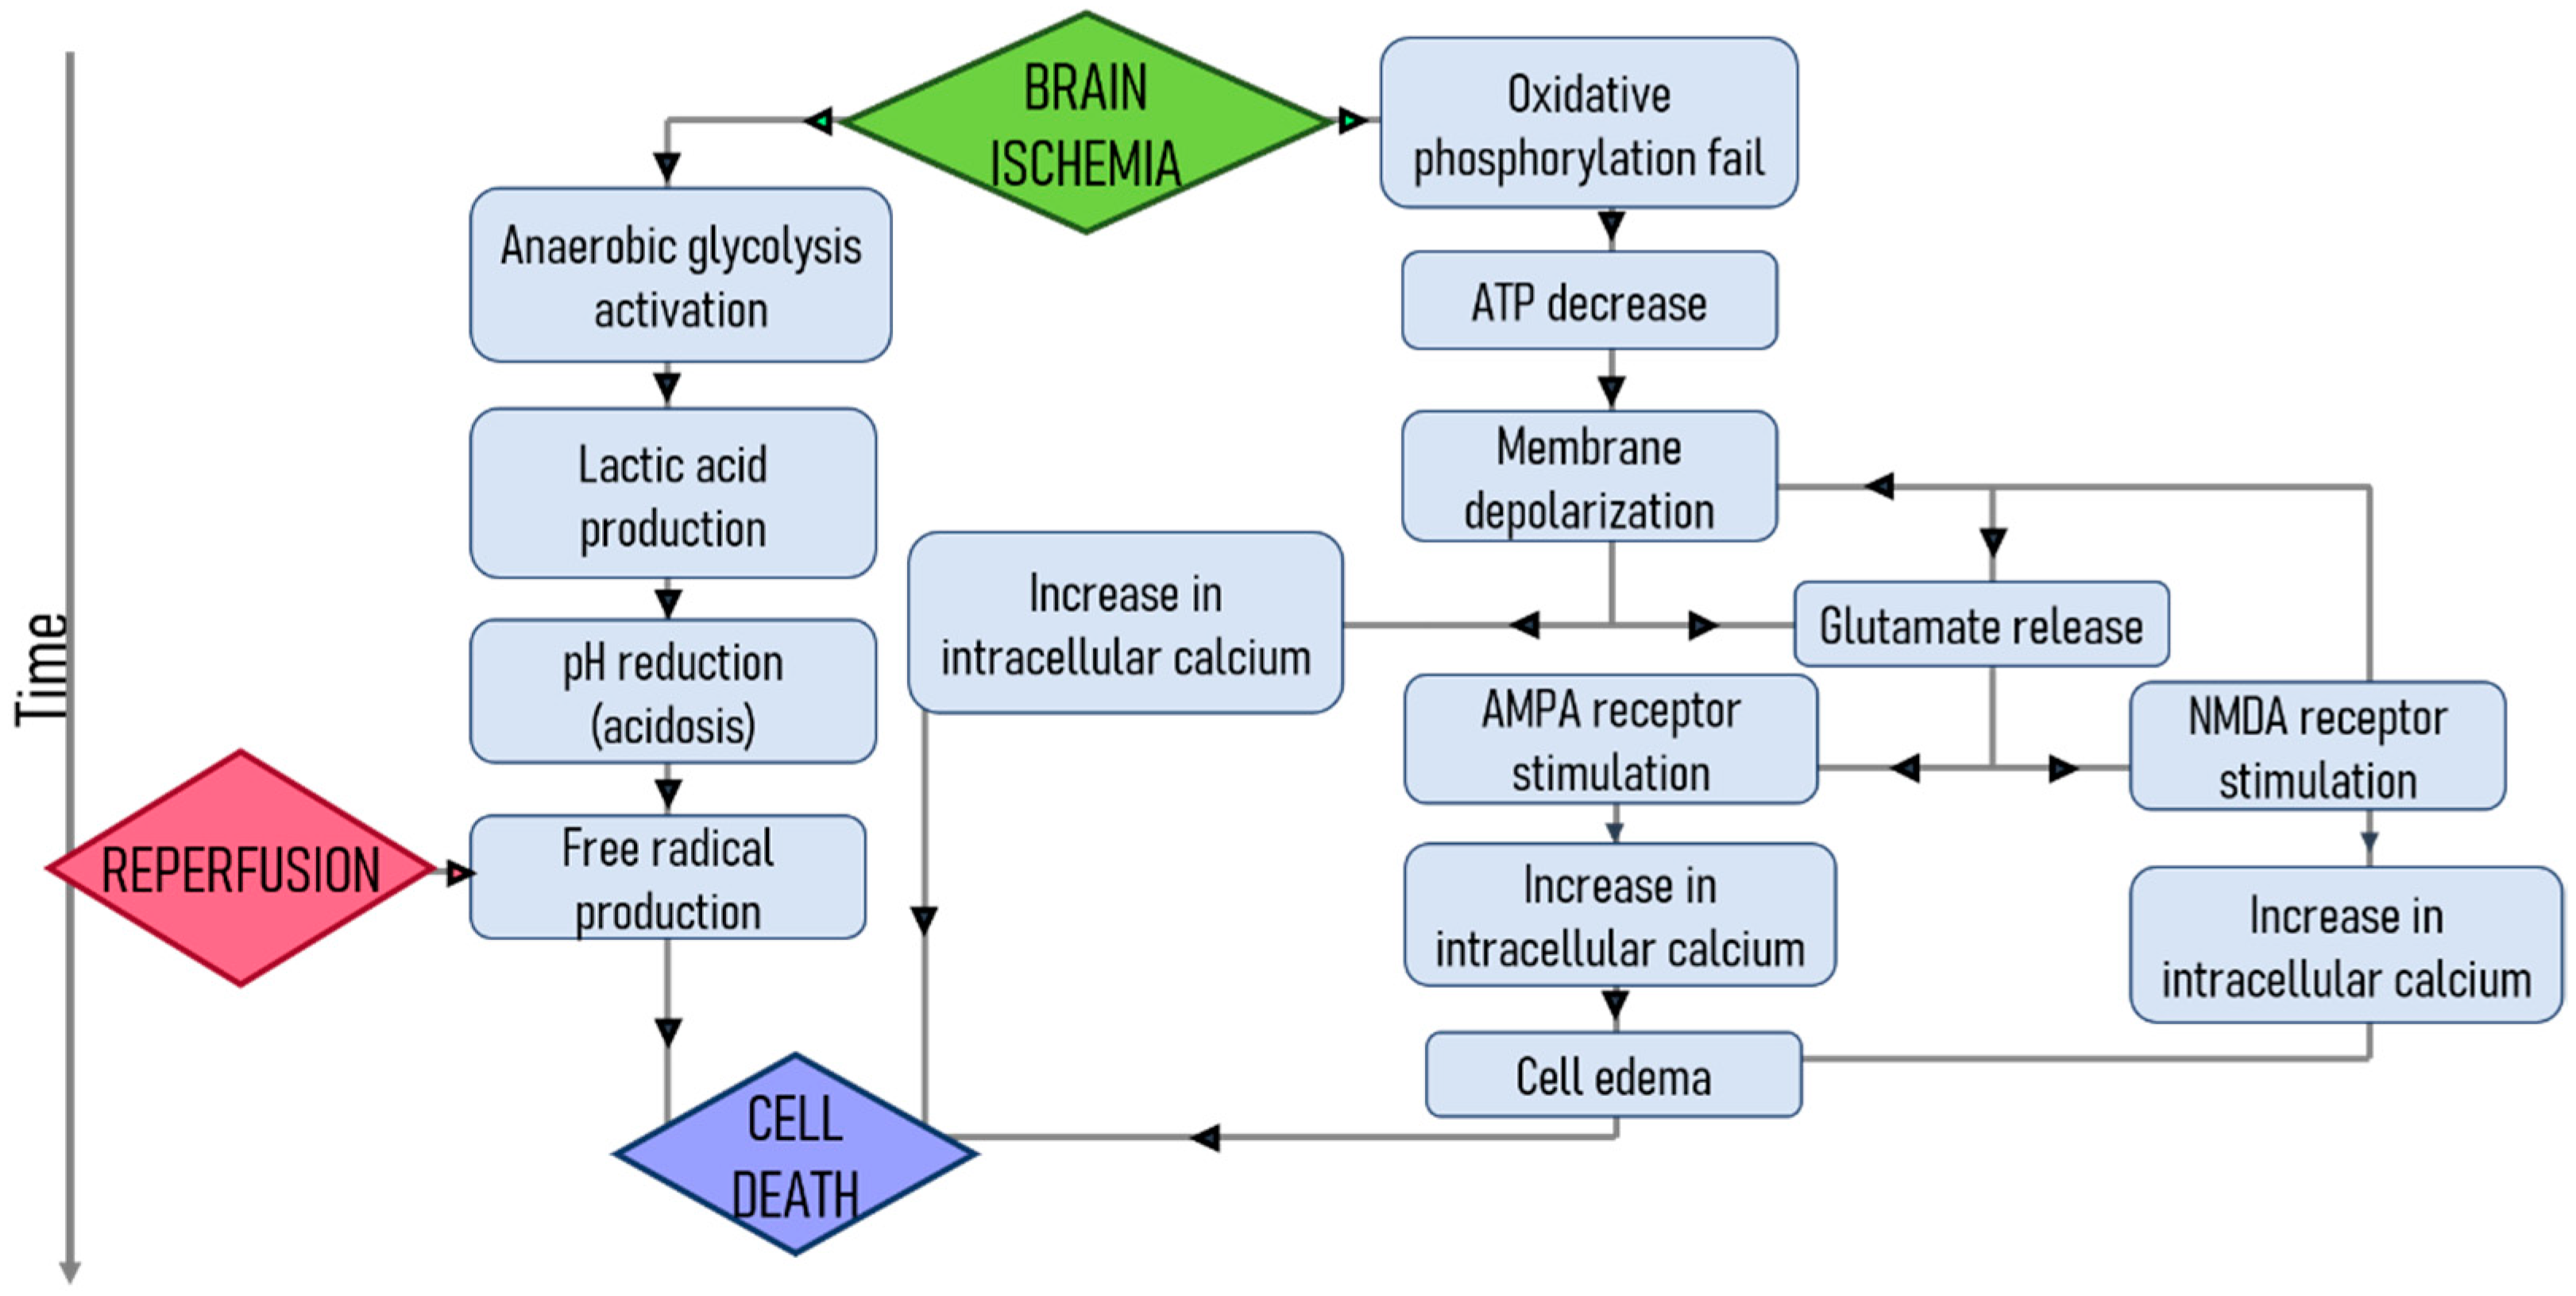

1.1. Stroke

4. Nanoparticles as a Therapy for Ischemic Brain Protection

4.1. Inflammation

4.2. Oxidative Stress

4.3. Glutamate Excitotoxicity